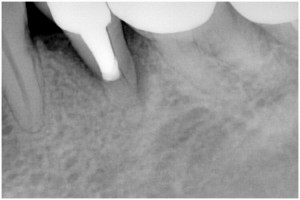

同拡大写真(根が破折しました)

抜歯後→インプラント埋入前

インプラント埋入後→被せ物装着

同パノラマ写真